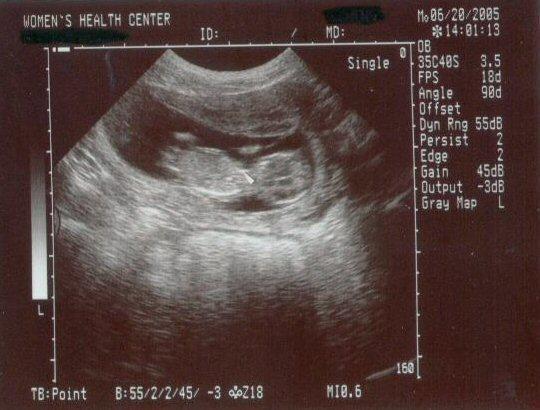

13 week ultrasound ~ The little one's getting bigger!